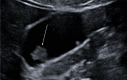

Gallbladder polyps are protuberances of the gallbladder wall projecting into the lumen. They are usually incidentally found during abdominal sonography or diagnosed on histopathology of a surgery specimen, with an estimated prevalence of up to 9.5% of patients. Gallbladder polyps are not mobile and do not demonstrate posterior acoustic shadowing; they may be sessile or pedunculated. Gallbladder polyps may be divided into pseudopolyps and true polyps. Pseudopolyps are benign and include cholesterolosis, cholesterinic polyps, inflammatory polyps, and localised adenomyomatosis. True gallbladder polyps can be benign or malignant. Benign polyps are most commonly adenomas, while malignant polyps are adenocarcinomas and metastases. There are also rare types of benign and malignant true gallbladder polyps, including mesenchymal tumours and lymphomas. Ultrasound is the first-choice imaging method for the diagnosis of gallbladder polyps, representing an indispensable tool for ensuring appropriate management. It enables limitation of secondary level investigations and avoidance of unnecessary cholecystectomies.